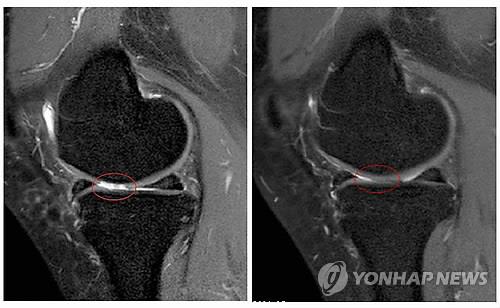

"자가지방세포 이식, 퇴행성관절염에 효과"

(서울=연합뉴스) 한성간 기자 = 자신의 지방조직에서 채취한 자가지방세포 이식이 퇴행성 관절염 치료에 효과가 있다는 연구결과가 나왔다.

세포치료·면역요법 국제컨소시엄(International Consortium for Cell Therapy and Immunotherapy)의 야로슬라프 미할레크 박사는 자가지방세포 이식이 퇴행성 관절염의 증상을 완화하고 손상된 관절을 일부 회복시키는 효과가 있다는 임상시험 결과를 발표했다고 의학뉴스 포털 메디컬익스프레스(MedicalXpress)가 16일 보도했다.

퇴행성 관절염 남녀환자 1천114명(평균연령 62세)을 대상으로 진행된 임상시험에서 각자에게서 떼어낸 지방조직 샘플에서 기질혈관분획(SVF)세포를 채취, 손상된 관절에 이식하고 12~54개월 동안 지켜본 결과 이 같은 효과가 나타났다고 마할레크 박사는 밝혔다.